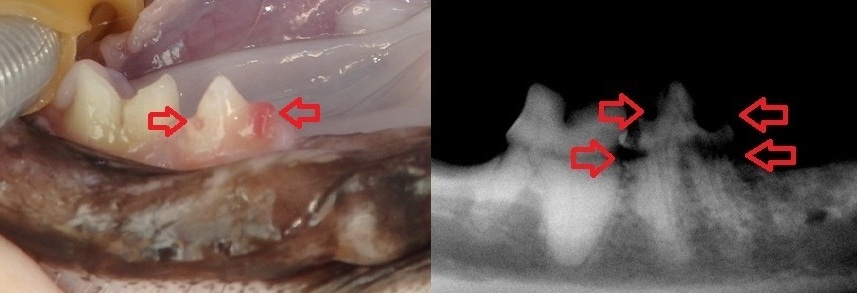

また、虫歯は少ないですが

破歯細胞性吸収病巣や

歯頚部吸収病巣と呼ばれる

歯が溶ける病気自体は

比較的よく遭遇します。

.jpg)

↑上の症例の歯の収集病巣

↑ほかの症例の歯の吸収病巣